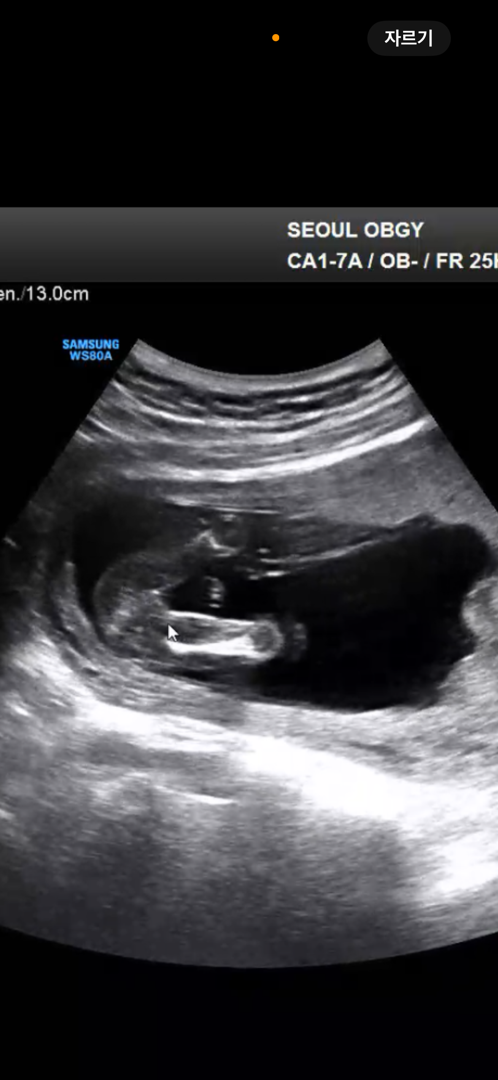

16주차 성별 봐주실분 계실까요!!!? :)

2주전에 병원 다녀왔는데 그때는 다리사이에 볼록한게 있어서 완전 아들이겠다 싶었어요! 그래서 2주후에 더 커지면 아들, 사라지면 딸일거라고 하셔서 오늘 다녀왔어요! 근데 오늘 보니 딱 보면 아무것도 없는데 살짝 돌리면 뭐가 동그랗게 보이더라구요! 대부분 아들맘들은 16주차에 누가봐도 존재감이 보인다고 해서 제 생각엔 딸 같은데.. 어때보이나요?

저도 이렇게되어있는데 병원에서 딸이래용~~~